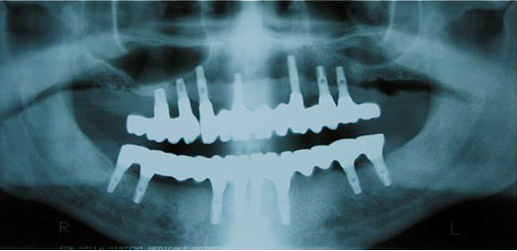

Caso 6 - Colocação de implantes dentários para reabilitação de desdentado total com prótese fixa em zircónio cerâmica.

![]() |